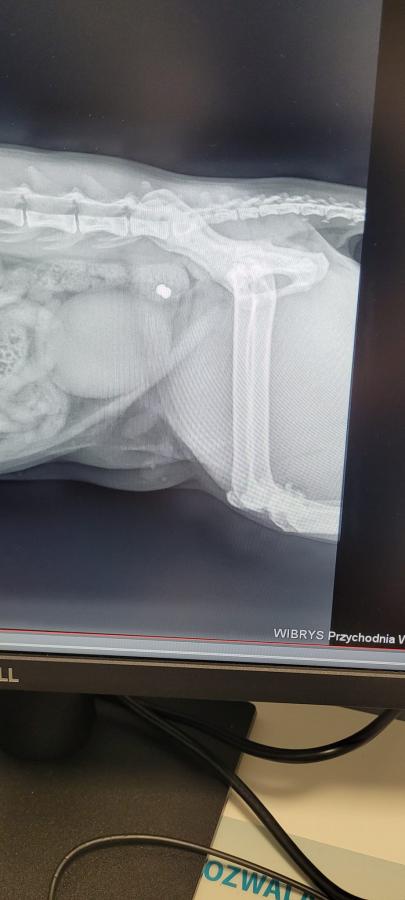

Opis galerii zdjęć: Zdjęcia kota Śnieżka, postrzelonego na ul. Białowieskiej, przed i po operacji usunięcia śrutu z łapki. Oferowanie nagrody za informacje o sprawcy oraz poszukiwanie rodziny adopcyjnej dla kota. Podkreślenie ochrony prawnej zwierząt i konieczności zgłaszania takich aktów do Stowarzyszenia Pan Kot.